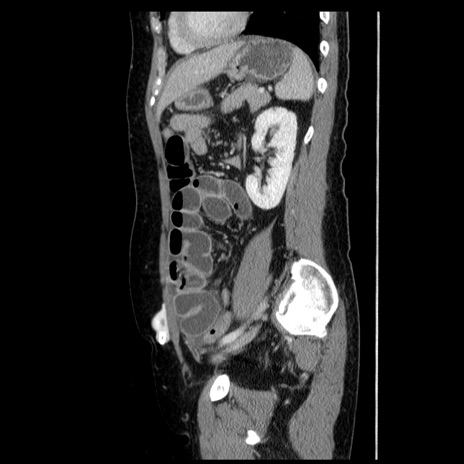

症例6(矢状断像)

【症例】50歳代女性

【主訴】下腹部痛

【現病歴】本日朝より下痢2回あり。 昼食を食べた後、嘔吐3回、下腹部痛認め、症状軽快せず、当院救急搬送。

最終食事:本日昼(生ものなし)。 昨日の夜、刺身を食ぺたとのこと。周囲に同様の症状の者なし。普段、排便は毎日あるとのこと。

【既往歴】卵巣癌術後(8年前に当院で卵巣摘出)

【身体所見】 意識清明、腹部:平坦、腸蠕動音→、やや硬、下腹部自発痛・圧痛あり、反跳痛あり、筋性防御なし。

【データ】WBC 16000、CRP 0.01